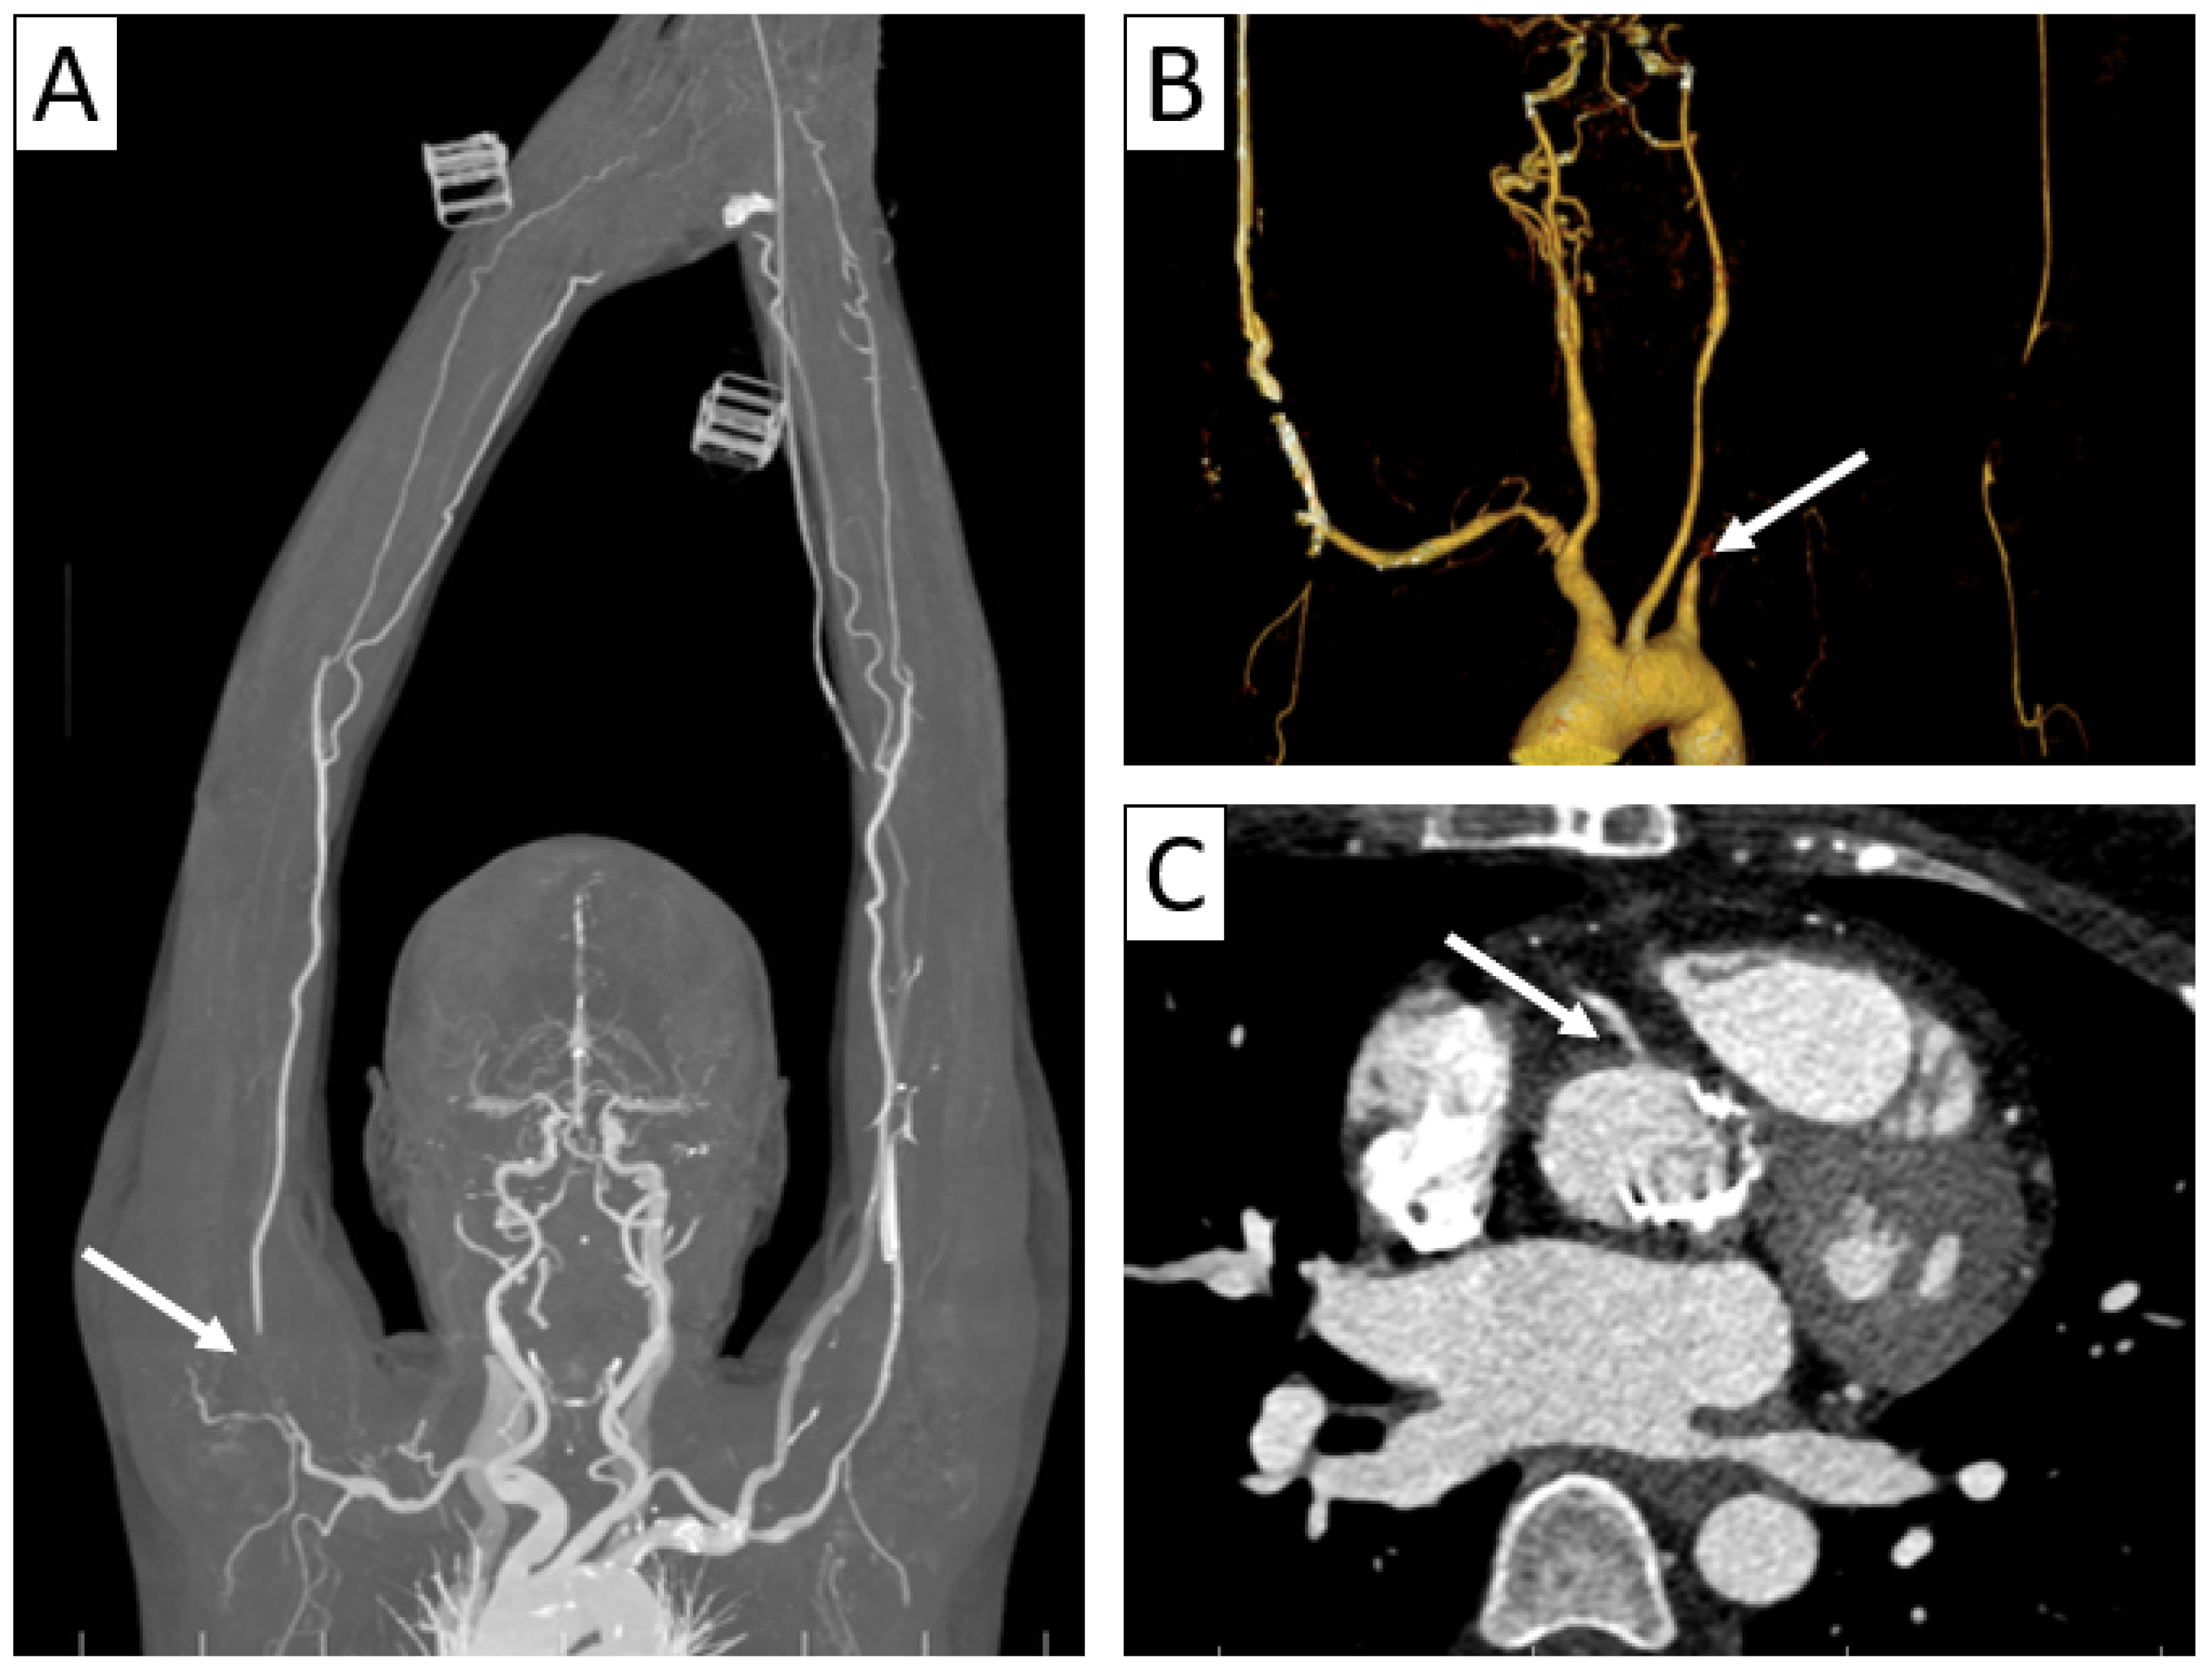

6.2.2. Takayasu Arteritis

| CTA | Circumferential parietal thickening Vessel wall enhancement | Circumferential parietal thickening Vessel wall enhancement Luminal stenosis or narrowing |